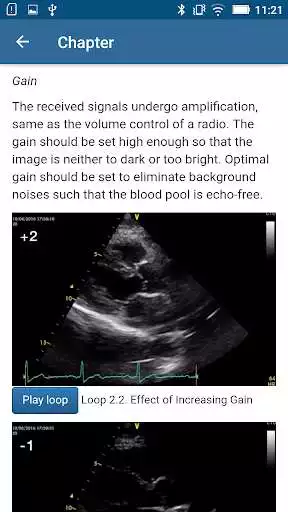

DESCRIPTION

Play this online game named Basic - Transthoracic Echocardiography.

This is the electronic course manual for registered participants of The Beyond BASIC - Transthoracic Echocardiography, The Chinese University of Hong Kong.Updates: